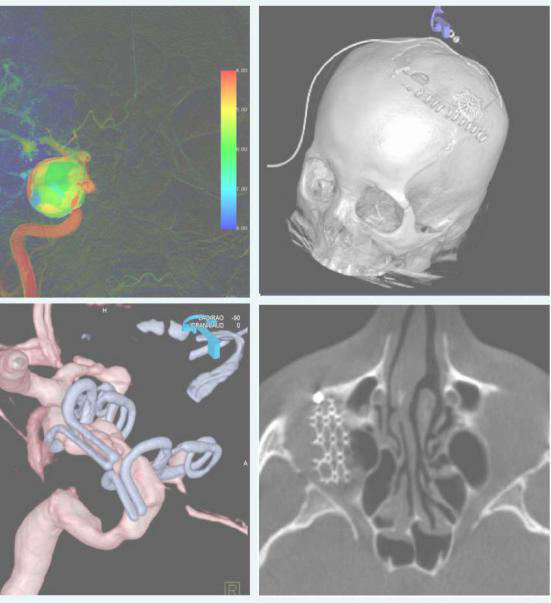

syngo Dyna4D展示特定时间点上的3D图像,对于脑血管畸形、血管瘤、动静脉瘘的结构、位置,并测量尺寸、分析供血动脉和引流静脉等。

神经及灌注成像PBV显示组织血容量灌注信息的功能学影像,并根据彩色 编码进行量化,病人无需转运到CT室就能得到病灶完整的灌注信息。

syngo DynaCT micro智能显示超精细结构,空间分辨率提高40%,可以观察0.1mm的结构。如图DynaCT micro观察眶底骨折植入钛网重建术,即时评估钛网植入位置。

颌面部血管瘤栓塞术,额面部血管瘤具有复杂迂曲的血供,DynaCT增强扫描帮助鉴别滋养血管,功能学影像Dyna PBV Neuro为瘤体栓塞终点做精准评估。